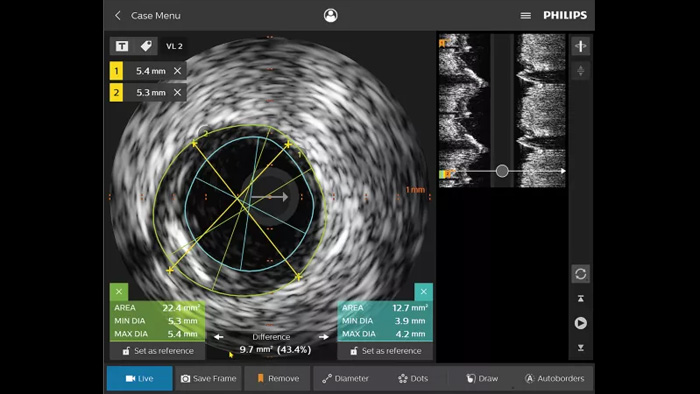

Intravascular ultrasound (IVUS) is a catheter-based imaging technology that allows physicians to visualize blood vessels from the inside out to aid assessment of presence and extent of disease. IVUS helps to decide, guide and confirm the right interventional treatment for each patient.

IntraSight provides more information through iFR/FFR and IVUS modalities in conjunction with the angiogram - controlled table side on the touch screen. It is built on a foundational platform capable of quickly adding new innovations to your lab.